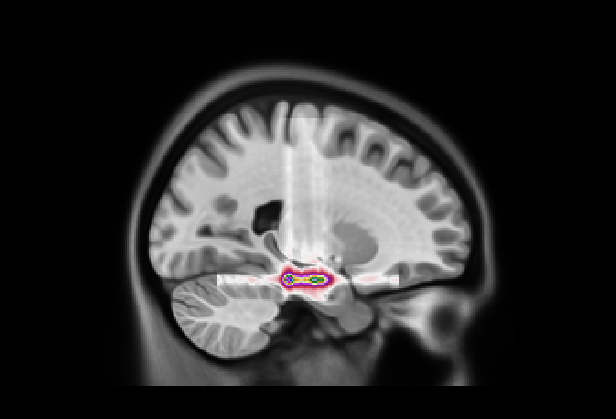

Refer to caption

(a)

(b)

Figure 8: GradCAM++ visualization of five slices for each plane selected randomly for our model (a) and Attention Transformer (b)

Figure 9: (Left) Visualization of mean 3D GradCAM++ map of entire dataset overlapped to MNI152 template with our model; (Right) Visualization of mean 3D GradCAM++ map of entire dataset overlapped to MNI152 template with Attention Transformer;

We also examined the interpretability of the Attention Transformer model proposed in (Altay et al., 2021). For comparison, we created 2D saliency maps using the GradCAM++ algorithm (Chattopadhay et al., 2018) across all three views and all five test sets from the different folds. These maps were combined to create a unified average 3D saliency map as outlined in Section 7. This method was also applied to generate equivalent results from the saliency maps produced using our diagnostic model. As shown in Fig. 8, the 2D maps produced by our method are generally sparser compared to those from the Attention Transformer. The method introduced in (Altay et al., 2021) employs a cross-attention mechanism via a Multi-Head. Therefore, it is plausible that the Multi-Head allows to generate 2D maps that align more meaningfully within the 3D context. This finding suggests that our approach may consider less contextual information from adjacent slices unless it is particularly relevant. In contrast, the cross-attention in the Attention Transformer might enable a more cohesive representation of the entire 3D space by considering both the local features within slices and their contextual interactions. This behavior is further clarified by creating 3D maps and overlaying them on the MNI152 template, similar to the attentional maps. As illustrated in Fig. 9 on the left, the 3D maps created using our model cover a broader and less concentrated area compared to those produced by the Attention Transformer, which are shown on the right. However, similar to the 3D attentional maps, both models predominantly focus on an area surrounding the hippocampus. As detailed in Table 9, both models identify key areas, such as the hippocampus and the amygdala, as significant. However, the emphasis on other regions varies markedly between the two. In the attention transformer model, there is a noticeable focus on the inferior lateral ventricles and the parahippocampal region, areas less emphasized by our model in this case. This result indicates that the Attention Transformer using cross-attention in combination with GradCAM can produce results similar to those obtained by our method with a 3D attentional map. As seen in Tables 8(a) and 9(b), the first four areas on which our model focused with our approach are the same as those focused on by Attention Transformer with GradCAM. In contrast, our model with GradCAM shows broader involvement with regions such as the superior and middle temporal areas, which are not as prominent in the other cases.